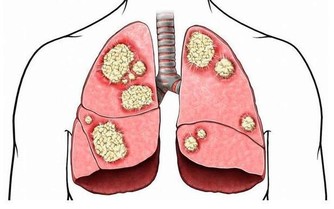

自2010年2月4日,因喉部總有異物感和頸部淋巴結腫痛看病。醫生給我做了淋巴結針吸,及甲功全項檢查。結果為甲狀腺球蛋白為351.正常值應該是0.針吸結果為淋巴有外癌細胞。考慮為轉移癌。2010年2月20日,在北京協和醫院確診為:甲狀腺癌晚期,已經轉移至肺部。CT胸片為有大量結節組織。多為5毫米以下為轉移癌。